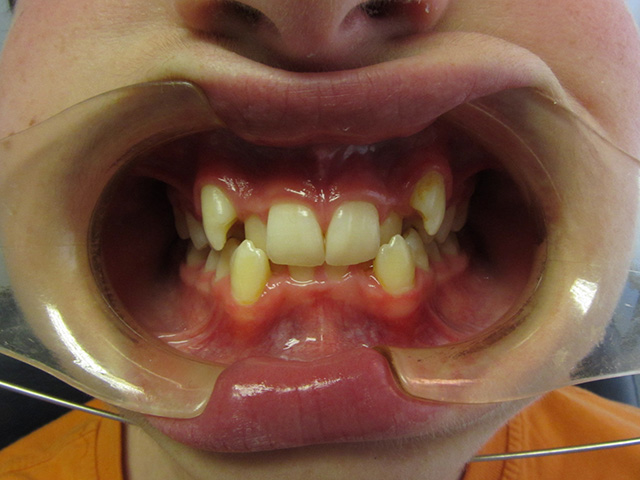

Ortodontzia, pilaketa ebakitzailea